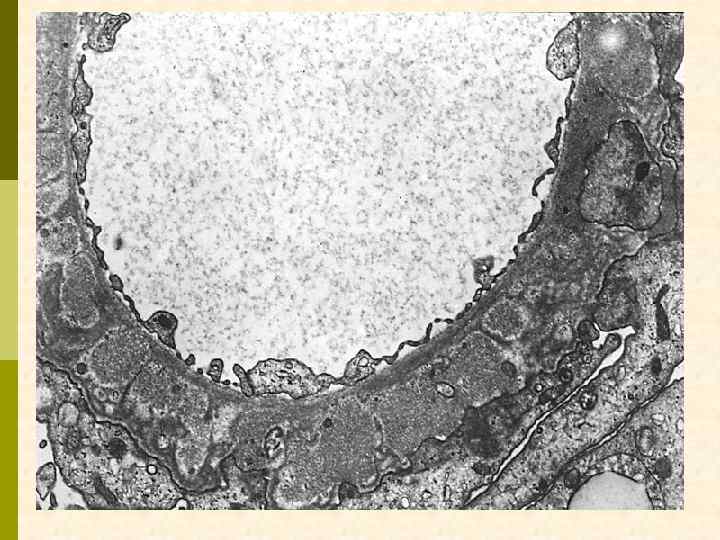

Электронноплотные (темные) депозиты на эпителиальной поверхности ГБМ (субэпителиальные). Каждый из них отделен друг от друга, а некоторые включены в вещество, подобное ГБМ (II–III стадия мембранозной нефропатии). Малые ножки подоцитов сливаются между собой.

By electron microscopy in membranous glomerulonephritis, the darker electron dense immune deposits are seen scattered within the thickened basement membrane. The "spikes" seen with the silver stain represent the intervening matrix of basement membrane between the deposits.